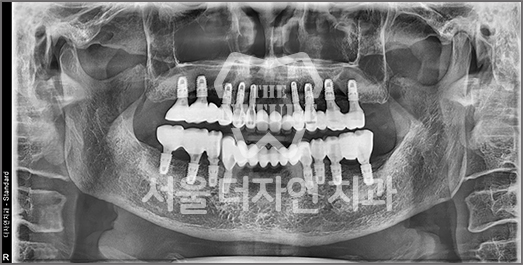

임플란트 재수술

처음보다 더 어렵고 까다로운

재수술 임플란트

잘못된 임플란트 수술과 잘못된 임플란트 관리는 부작용이 발생시킬 수 있으며, 통증을 동반하게 됩니다. 임플란트 재수술은 기존 임플란트를 제거 후

새롭게 잇몸뼈를 만들고 알맞은 잇몸 형태를 잡아내어

새 임플란트를 식립하는 시술입니다.

• BEFORE: 2021.11.02

• AFTER: 2022.01.19

타 치과에서 식립한 임플란트가 너무 멀리 잘못 심겨져 있어

올바른 위치로 재수술한 케이스입니다.